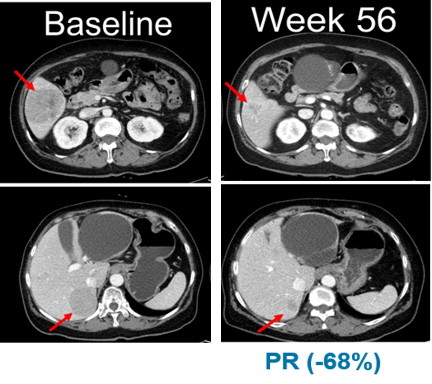

적응증 확장 임상의 NRAS 변이 흑색종 연구에서는 13명의 환자 중 5명이 부분반응(PR)을 보였으며, 최고반응률(BORR)은 38.5%로 나타났다.

13명의 환자 중 11명은 이전에 면역관문억제제(CPI)를 투여 받았으며, 면역관문억제제 투여 환자군 대상 최고반응률(BORR)은 45.5%로 확인됐다. 무진행생존기간(PFS)의 중간값은 7.3개월이다.